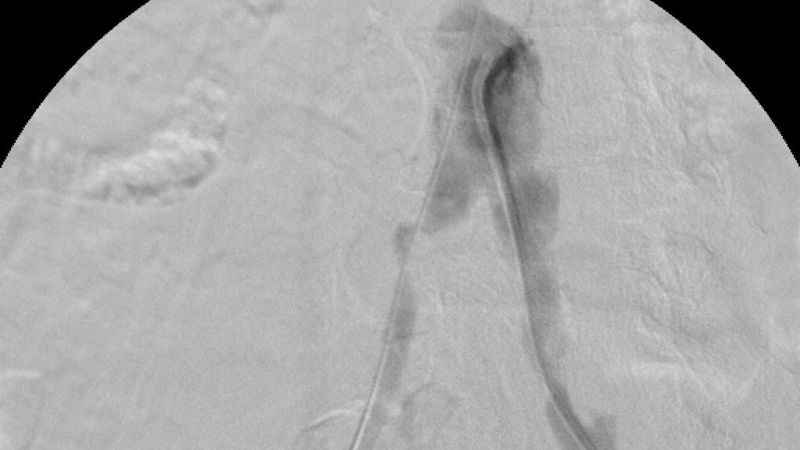

Özellikle anjiyografik yöntemlerle ameliyat gerektirmeden tedavi olanağı sunuluyor. Balon, stent ve damar tıraşlama yöntemleri, bu tedavilerin başında geliyor. Bu tedavilerde kullanılan tıbbi cihazların üretimi bir zamanlar yalnızca belirli ülkeler tarafından yapılırken, artık Türkiye kendi cihazlarını üreterek dünya sahnesinde yer alıyor. Bu alanda yaşanan en büyük yeniliklerden biri de "stent greft" teknolojisi oldu. Üretimi dünyada sadece 5 ülke tarafından yapılan stent greft üretimi ile Türkiye, tıbbi inovasyon alanında tarihi bir başarıya imza attı. Bu büyük adım Türkiye'nin sağlık teknolojilerindeki gelişimini küresel arenada da tescilledi.

Türkiye'nin ilk yerli stent grefti Bezmiâlem Vakıf Üniversitesi Tıp Fakültesi'nde Prof. Dr. Cengiz Köksal ve Doç. Dr. Emre Selçuk'un öncülüğünde Artven koordinasyonuyla bir hastaya başarıyla uygulandı. Doç. Dr. Emre Selçuk, bu büyük adımı şöyle değerlendirdi:

"Stent-greft teknolojisi, damar tedavilerinde kritik bir rol oynuyor. Damar balonlaşması veya yaralanma riski olan hastalarda bu teknolojinin önemi daha da artıyor. Artık bu teknolojiyi Türkiye'de üretiyor olmamız, operasyon başarımızı artırmanın yanı sıra, hasta güvenliğini de üst seviyelere taşıyacaktır. Türkiye'nin tıbbi alandaki bu başarısında yer almaktan büyük gurur duyuyoruz. Atlas Stent Greft, Türk mühendisliğinin ve Türk doktorlarının inovasyonunun ne kadar ileri seviyede olduğunun bir göstergesidir."